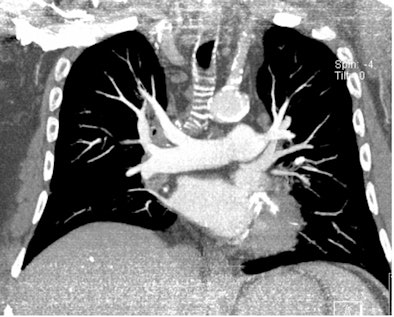

| All three CT images are from the same female patient weighing 95 kg with no pulmonary emboli. Above are two coronal maximum intensity projection (MIP) images, and below is a 1-mm thin transverse slice. At this body weight, 80-kVp CT angiography protocols provided good image quality and a high enough diagnostic confidence to exclude pulmonary embolism. All images courtesy of Dr. Zsolt Szücs-Farkas. |